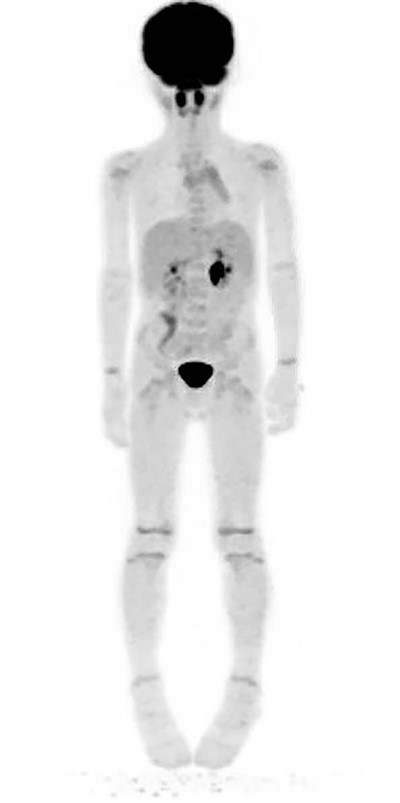

Two weeks later, the patient reported no further symptoms at follow-up. However, due to the inconclusive pathology report, a bone marrow biopsy was scheduled to rule out a potential lymphoma. Twenty days following the clinic visit, the patient underwent another MRI as well as the bone marrow aspiration. This MRI demonstrated significant improvement in the size of the mass and no lymphadenopathy. The bone marrow biopsy demonstrated mild hypocellularity and nonmalignant characteristics (Table 2). Flow cytometry performed on this sample was negative for neoplasm (Table 3). A positron emission tomography (PET) scan completed 4 months from initial presentation demonstrated no increased uptake concerning for a neoplastic process (Fig. 3). The patient had no concerning symptoms and reported no further complaints on repeated follow-up.

PET scan performed 4 months following surgical removal of the mass showing no abnormal uptake in the right neck/supraclavicular region.